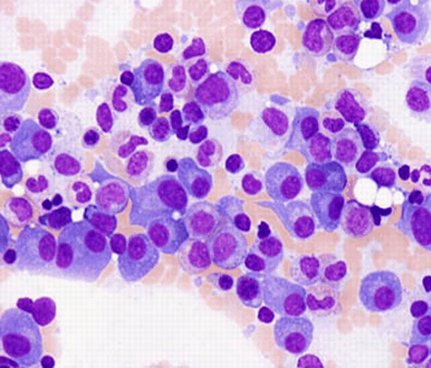

63/male with abdominal lymphadenopathy. DQ gave the initial clue to hemepath diagnosis. Positive CD3/5/7/25. CD30 diffuse, ALK1/CD20 negative. CD30+ Mature T-cell lymphoma. D/D ALCL or ATLL HTLV1 is positive! #cyto #hemepath #PathTwitter Kevin Kuan Yanhua Wang #bridgingcytoheme